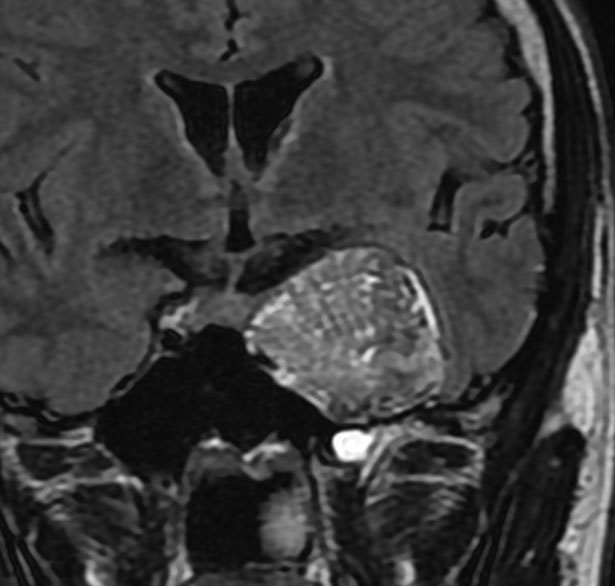

前頭蓋底類皮のう胞

蝶形骨平面から鞍結節上に発生するもので多いタイプです。左側のT2強調画像で内容物がまだらに見え,右側の拡散強調画像で高信号(白い)に見えるので診断確定です。内頸動脈や前大脳動脈や穿通枝などとの癒着が強いものが多いので剥離は難しく要注意です。ある程度の大きさを超えると経鼻内視鏡手術では摘出できません。この腫瘍は脳槽内にあるので,一回の手術でのう胞の壁も含めて全部摘出しなければなりません。そうしないと,手術後に内容物(皮脂と汗とケラチン)が髄液の中に産生されて漏れ出て,難治性の水頭症になります。